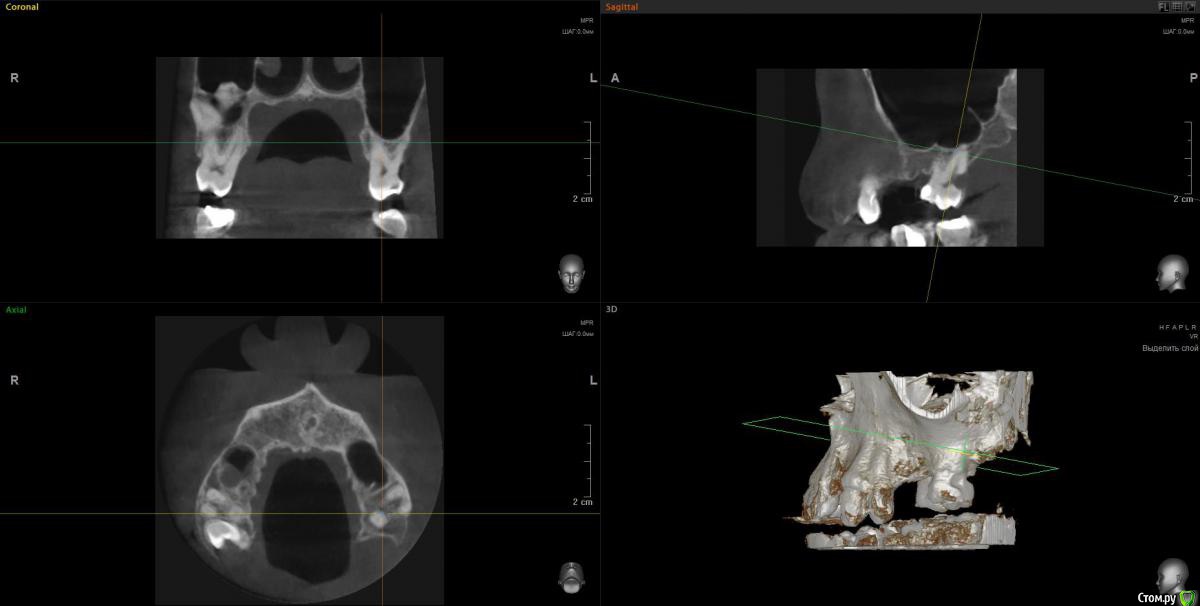

Просьба ко всем не равнодушным! Глянуть КТ верхней челюсти, 27 зуб  и место где удалили 16, может ещё где-то могут быть проблемы.  На фото видно где покраснение на дёснах, в этих местах возникают боли при движении головой. Бывает боль слева если засыпаю на левой стороне. Набуханий или флюсов нигде не видно.Прошу делиться мнениями, для меня это очень - очень важно. Стоматолог визуальных проблем на месте удалённого зуба не видит, всё зажило.

По данным КТ в зоне удалённого зуба 16 ничего особенного, разве что, ретенированный (непрорезавшийся) зуб 18.

Зуб 27 требует внимания, необходим очный осмотр.

Также стоит обратить внимание на зубы 21 и 24